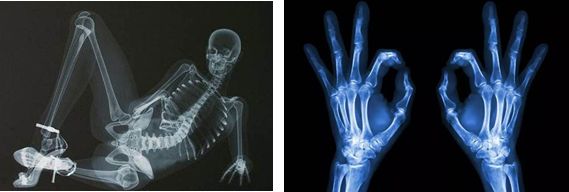

X光——把东西“压扁”看

就是用 X 光给你的身体拍了一张照片的检查方式。所以 X 光也叫拍片子。

(x射线长这样哦)

X光会穿过人体,不同组织吸收形成不同的曝光,遇到被遮挡的部位,底片上不会曝光,洗片后这个部位就是白色的。

就像一片面包或一块棉花,看不到里面的纤维纹理,但用手压瘪了会清晰一些。所以其明显的优点就是适合平面透视,而最大缺点是受制于深浅组织的影像相互重叠和隐藏,有时需要多次多角度拍摄X光片。

它可对人体胸部、腹部、腰椎、四肢等部位进行正位、侧位进行摄影诊断。